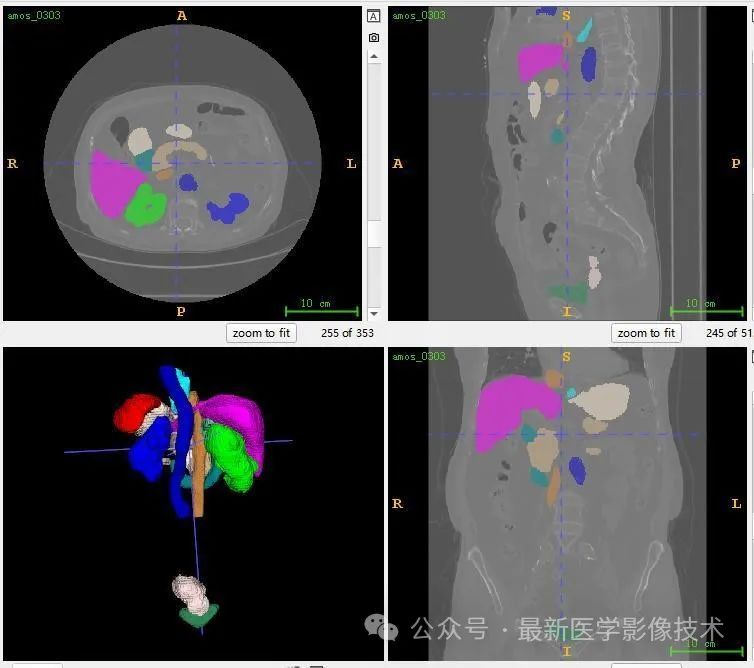

13、测试集分割结果

12、验证集分割结果

左图是金标准结果,右图是预测结果。